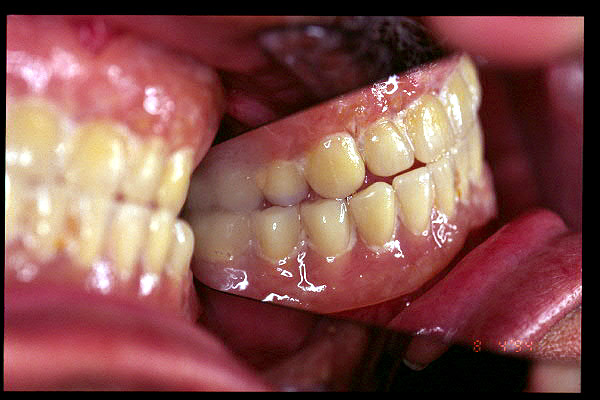

CM Desgaste por bruxismo, presencia de cálculo